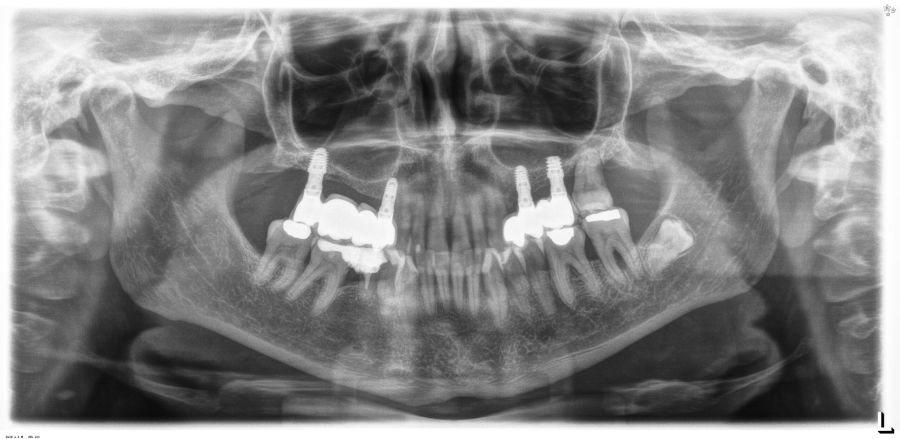

Transcurridos 6 meses desde la carga inicial progresiva, se puede elaborar la prótesis definitiva, trasladando los parámetros de la prótesis provisional (Figura 27). La paciente continúa en seguimiento durante un año, realizándose radiografías de control para el monitoreo del hueso crestal, sin encontrarse pérdida ósea asociada en ninguno de los implantes (Figuras 28-29).